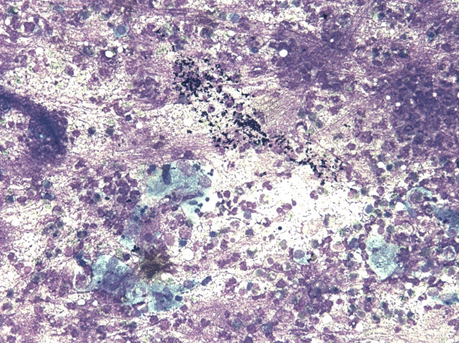

A 16-year-old girl presented with swelling in the right lobe of thyroid. There were no generalized symptoms like fever, malaise, night sweats and weight loss. There was no history of difficulty in deglutition or voice change. On clinical examination there was a single abscess of size 4x4 cm in right lobe of thyroid moving with deglutition. The margins were well demarcated, smooth surface, non-tender and overlying skin was normal with a tattoo mark on it (Figure 1). There were no clinical features of hypothyroidism or hyperthyroidism. Routine blood investigations were done; hemoglobin 11.0 g/dl, total leucocytes count 8600/mm3, neutrophils 67/mm3, lymphocytes 31/mm3 and eosinophils 2/mm3. The erythrocyte sedimentation rate was 20 mm. The Mountax test was highly positive more than 10 mm in diameter. Thyroid function tests T3, T4, TSH were normal. X-ray chest was normal. Ultrasonography of neck revealed a 50x45x20 mm solitary nodule in the right lobe of liver. This solitary thyroid nodule was showing thick irregular wall with central necrosis reported as suspected thyroid abscess. Magnetic resonance imaging scan of the neck showed a lesion of intermediate signal intensity due to presence of dense inflammatory cells and granulomas with central necrosis (Figure 2). A doubt about carcinoma of thyroid was placed as differential diagnosis. The CECT scan of neck was done to rule out carcinoma of thyroid gland. This was helpful in diagnosis of tubercular thyroid abscess as localized caseous lesion in right lobe of thyroid (Figure 3). Fine needle aspiration from this solitary thyroid nodule was done to confirm the diagnosis. The stained smears revealed degenerated and intact neutrophils, and macrophages in serofibrinous background. A few epithelioid granuloma and multinucleated giant cells are also seen suggestive of tuberculosis with central caseous necrosis. Ziehl–Neelsen staining with 20% H2SO4 was noncontributory (Figure 4). From the central part of swelling about 2 ml of thick yellow color pus was aspirated as shown in Figure 5. The smears prepared from this pus did not show any acid-fast bacilli. After aspiration the swelling decreased in size. The cytological diagnosis of tubercular abscess was made. The patient was put on antitubercular treatment with four drug regimens. The swelling decreased in size in next three months (Figure 6). She was asked to continue on three drug regimens for another six months leading to complete resolution of swelling. | ||||||